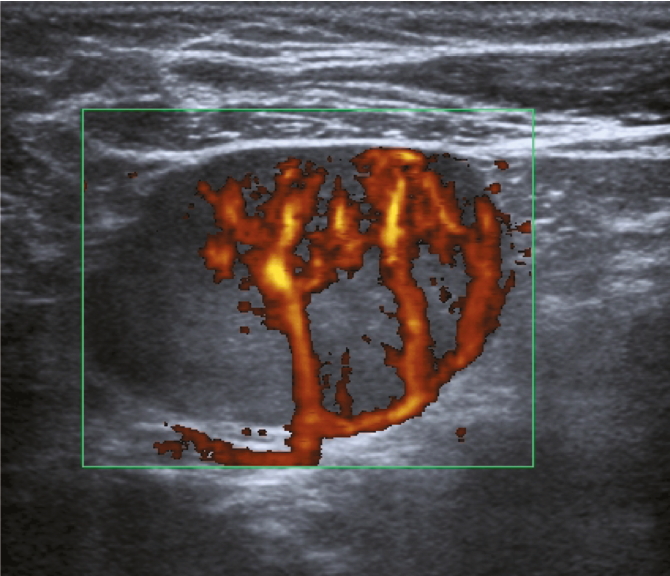

При цветовом и энергетическом допплеровском картировании кровоток в метастатически измененных лимфатических узлах визуализируется в 93% наблюдений. При этом выявляются извитые, разнокалиберные, ветвистые, хаотично расположенные сосуды (рис. 4).

Рис. 4. Энергетическое допплеровское картирование подмышечного лимфатического узла с метастатическими изменениями.

Fig. 4. Color Doppler Energy Mapping of metastatic axillary lymph node.